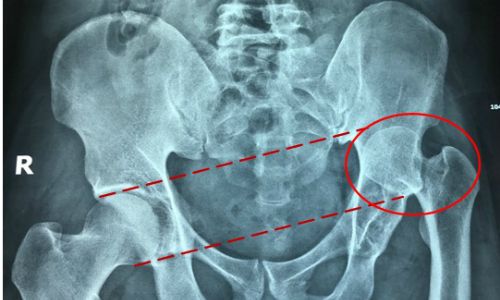

Phần hông hơi xoắn lại khiến khung chậu mất thăng bằng, từ đó gây áp lực lên cột sống và dẫn đến các cơn đau. Ngồi bắt chéo chân liên tục hàng ngày, hàng tuần là một trong những nguyên nhân chính dẫn đến đau lưng, cổ và thoát vị đĩa đệm

Dây thần kinh hông là dây hỗn hợp lớn nhất của cơ thể. Mọi áp lực gây ra bởi tư thế ngồi bắt chéo chân đều có thể khiến dây thần kinh hông bị tê, thói quen này kéo dài lâu dần có thể dẫn đến tổn thương.